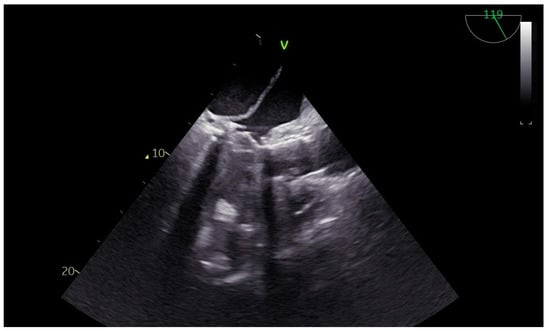

Advanced hemodynamic monitoring as per local protocol was applied with cannulation of the right radial and femoral arteries as well as establishment of peripheral access with two (wide) 16 G cannulae. Baseline invasive blood pressure before induction was 145/60 mmHg. Induction to anesthesia was uneventful without any signs of hemodynamic instability, using balanced anesthetics for the maintenance of general anesthesia too. A central line and pulmonary artery catheter were placed in the right internal jugular vein. Continuous cardiac monitoring and cerebral oximetry monitoring were applied while depth of anesthesia was monitored with the Bispectral Index. Intraoperative transesophageal echocardiography (TEE) was used and confirmed the findings of TTE, especially with a heavily calcified mitral valve annulus (Figure 1). Standard bicaval extracorporeal circulation through sternotomy and mild systemic hypothermia (32 °C) were used. Myocardial protection was made by a combination of antegrade and retrograde cold hyperkalemic blood cardioplegia. Cardiopulmonary bypass time was nearly two hours. The separation from cardiopulmonary bypass was initially smooth with minimal vasopressor support (blood pressure > 85–90/45 mmHg). A few minutes after the protamine administration an episode of profound hypotension caused major hemodynamic instability (blood pressure > 55–60/35 mmHg), which was related to the protamine side effects. However, since it persisted, regardless of the treatment with vasopressors, a thorough reassessment with the TEE was performed. This dynamic investigation revealed an obvious flap fluctuating in the left atrium, suggestive of a dissection flap in the chamber (Figure 2). (The dissection flap size was at least 7.2 cm. There was difficulty in the precise measurement of its dimension because the left atrium roof could not be visualized.) Otherwise, the two new prosthetic valves were well seated without any residual regurgitation (Figure 3 and Figure 4). The most plausible explanation for the presence of the dissection flap was the earnest mitral valve replacement performed in the setting of extensive mitral annular calcification. Hemodynamic stability was achieved with boluses of vasopressors (phenylephrine) and noradrenaline and adrenaline infusions. Since the patient was relatively stabilized under this support, the chest was closed and he was taken to the intensive care unit with a target for systolic blood pressure less than 100–120 mmHg for the first twenty-four hours (Table 1).

Figure 4. Postoperative Perceval well-sited mitral valve replacement.

A sutureless rapid-deployment Perceval M (LivaNova, London, United Kingdom) aortic valve bioprosthesis was implanted through an aortic transverse incision after performing annular debridement of all calcification. The mitral valve was exposed by opening the dome of the left atrium dissecting the Sondergaard’s groove. Severe calcification of the mitral annulus with extension to the myocardium and the papillary muscles was identified. Debridement of all calcification was attempted, leaving the calcified parts penetrating the cardiac muscle in order to avoid the risk of rupturing the left ventricular wall. A Mosaic™ mitral valve bioprosthesis (31mm, Medtronic, Inc.; Minneapolis, Minn) was implanted with interrupted sutures of 2-0 Ethibond Excel® (Ethicon, Johnson & Johnson company; Somerville, NJ, USA) and reinforced by subannular Teflon felt pledgets. Destruction of the annular anatomy during debridement in the area between 8 and 11 o’clock made suture positioning extremely challenging. This was most likely the site from where the dissection may have originated.